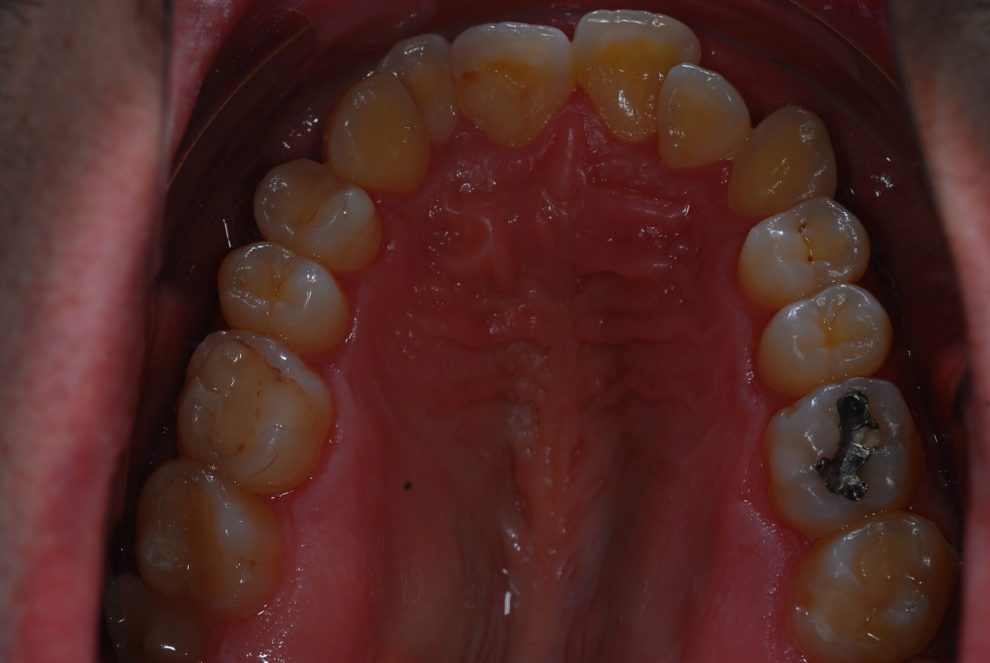

Nuestro paciente Manuel Vergara Gil acudió a nuestra clínica, y se le hizo una Ortodoncia.